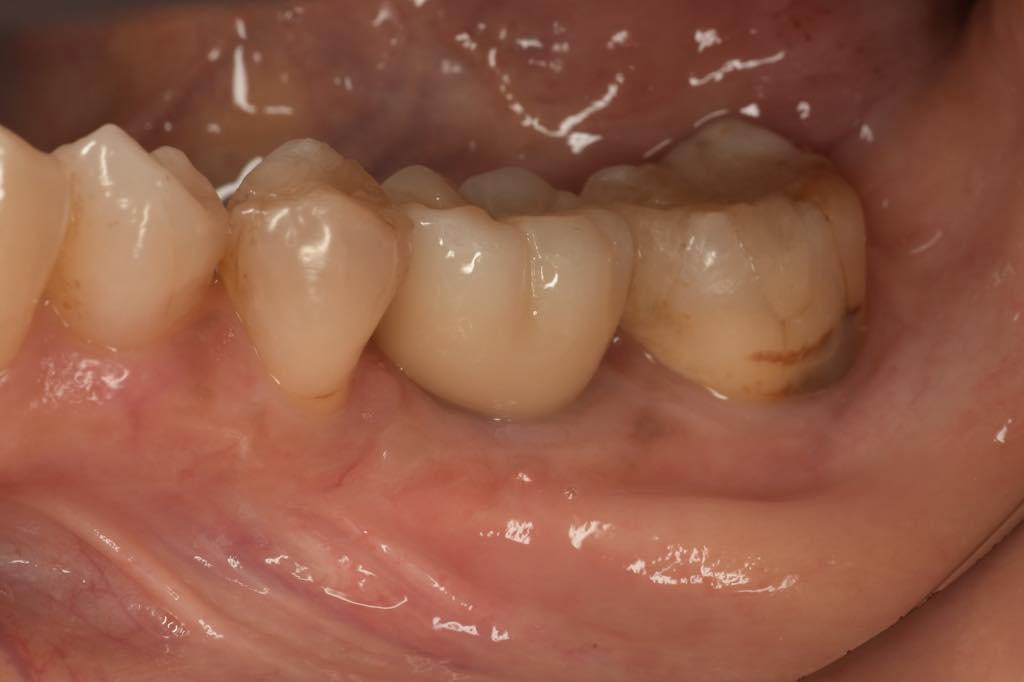

CASE 02

| 主訴 | 右下奥歯が欲しい |

| 治療内容 | 右下6番 インプラント治療 |

| 治療回数 | 8回 |

| 治療費用 | ¥390,000 |

| 想定される副作用 | 腫れ、痛み |